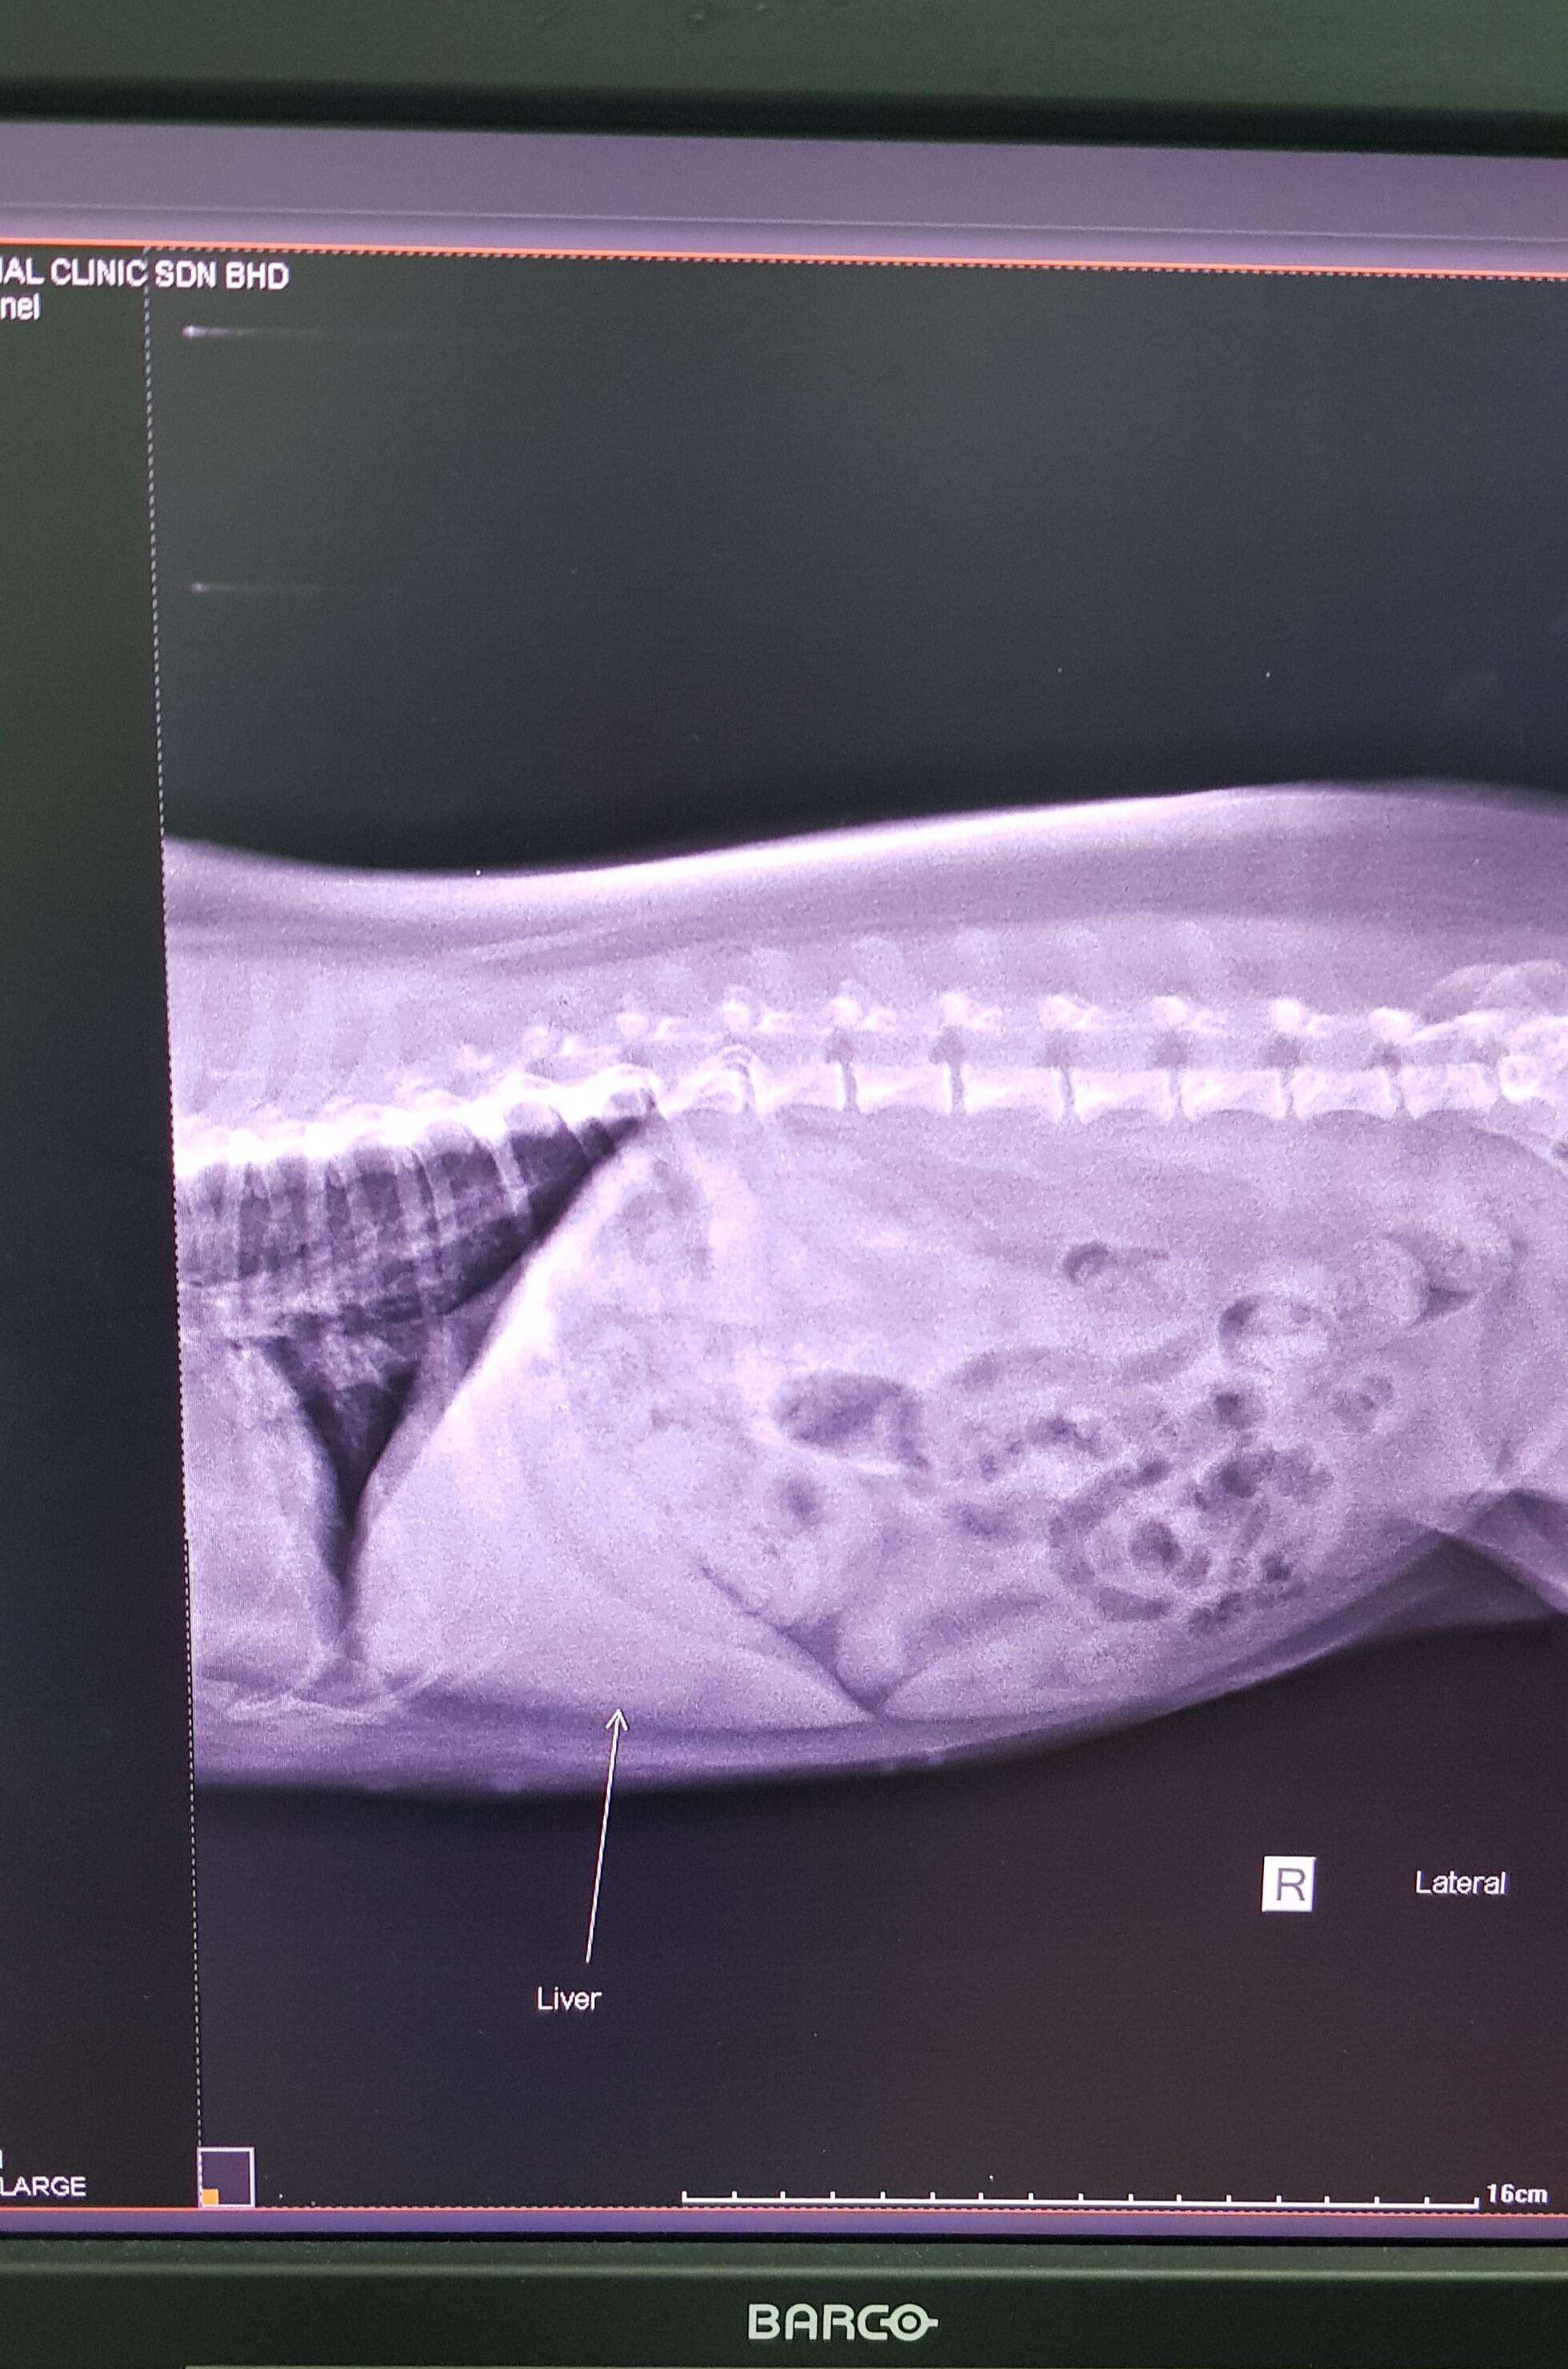

Doctor, I would really appreciate a consultation/ second opinion for my mixed terrier, 11 years old, spayed female. Attached herewith 2 views of her liver and result blood test . She was diagnose with liver inflamed and presribed Demanarin for 2 week. And Doxycycline for antibiotics pre existing positive E-Cams. The reason to vet visit is she had been very good appetite lately, and gain weight. However, her stomach area had gotten bigger/swollen and im worried. Thank you very much in advanc

Hello. Her liver values are not bad at all, & her liver does not look enlarged. You might want to request a test to look at bile acids & perhaps an abdominal ultrasound to see if the x-ray has missed something in the abdomen. Finish the Doxycycline, & see if she truly has Ehrlichiosis or if this is just a red herring. Thanks for using Petco Pet Education Center, formerly Petcoach.